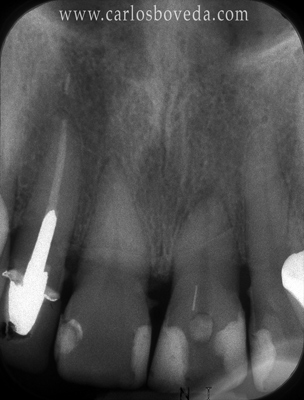

17